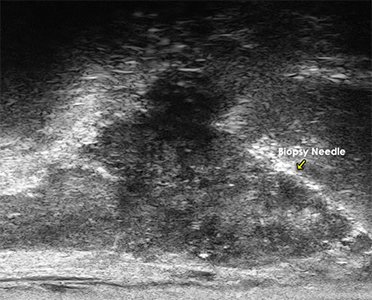

The 29 MHz ExactVuTM system facilities resolution down to 100 microns – and enables

detailed visualization in real-time of the prostate anatomy and characterization of

the prostatic tissue.

The following are select cases that are routinely derived from the ExactVuTM

micro-ultrasound platform and verified with pathological results.